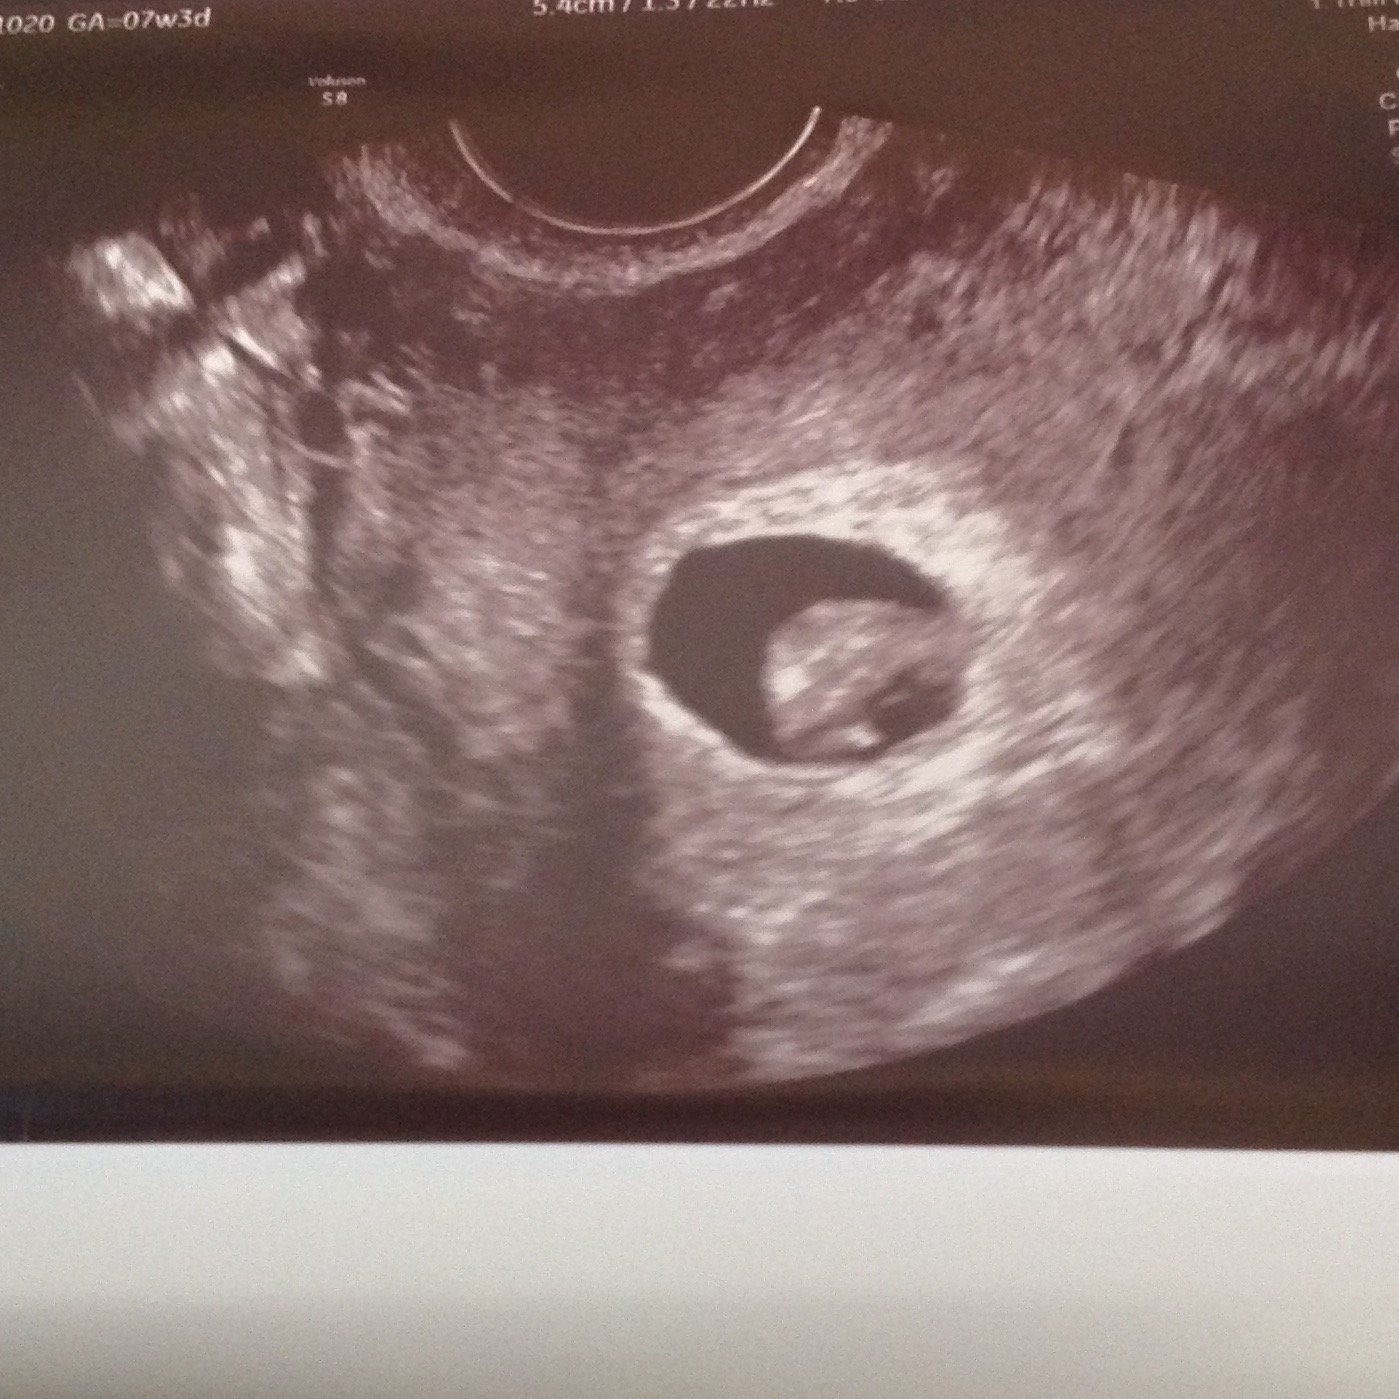

7 weeks. She was zoomed in pretty tight to try to see a membrane. She's worried they are mono-mono since they are so close, but I know it's too early to see it